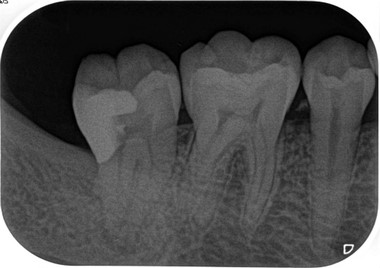

【症例】智歯による第2大臼歯遠心カリエス

(EEデンタルブログより引用)

?毎度おなじみのエアースケーラー用チップを使用してチマチマ削ります。

(カボ・ナカニシのダイヤル調整型を使い、パワー設定は基本2で使用してください)